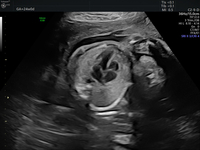

Ersttrimesterscreening

Das Ersttrimesterscreening ist die erste große Ultraschalluntersuchung in der Schwangerschaft und findet zwischen 12.-14. Schwangerschaftswoche statt.

Teil der Untersuchung ist einerseits die Berechnung eines individuellen Risikos für die häufigsten Chromosomenstörungen – Trisomie 21 (Down Syndrom), Trisomie 18 (Edwards Syndrom) und Trisomie 13 (Pätau Syndrom). Das Risiko wird Anhand des Alters der Patientin und spezifischen Ultraschallmarkern (Nackentransparenz, Nasenknochen, spezifische Blutflussmuster) berechnet.

Zudem werden die Entwicklung des Kindes und seine Organe untersucht. Dabei wird  großen Wert auf das kindliche Herz gelegt, denn viele Herzfehler können bereits zu diesem frühen Zeitpunkt erkannt werden, obwohl das Herz zu diesem Zeitpunkt erst so groß ist wie ein Reiskorn.

Der Vorteil des Ertstrimesterscreenings ist die frühe Entdeckung von angeborenen Entwicklungsstörungen. Bei optimalen Sichtbedingungen können die Ärzte einen Großteil der Fehlbildungen schon im 1. Trimester sehen. Durch das Entdecken von Auffälligkeit in diesem sehr frühen Stadium der Schwangerschaft haben die Eltern ausreichend Zeit, um sich von den erfahrenen Ärzten der Praxis, Humangenetikern, Kinderärzten, Kinderchirurgen, Kinderkardiologen und weiteren Spezialisten beraten lassen und dann die richtigen Entscheidungen über den weiteren Schwangerschaftsverlauf zu treffen.

Besonders sinnvoll ist das Ersttrimesterscreening bei Risikoschwangerschaften (Diabetes, Bluthochdruck, Autoimmunerkrankungen, Mehrlinge etc.) Hier lassen sich zudem die Risiken für eine Frühgeburt oder eine hypertensive Schwangerschaftserkrankung (Schwangerschaftsvergiftung) individuell abschätzen und noch im ersten Trimester einen „Fahrplan“ für die Schwangerschaft erstellen.